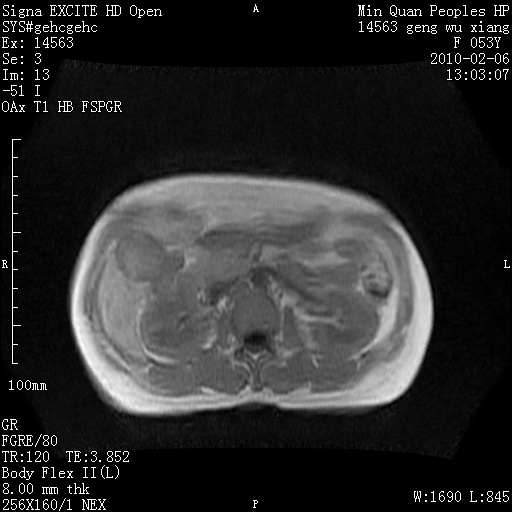

标题: MRI2762:胆道梗阻原因?

f,53y,全身黄染多日。

高位胆道梗阻 胆管癌可能性大

支持 高位胆道梗阻 胆管癌可能性大。